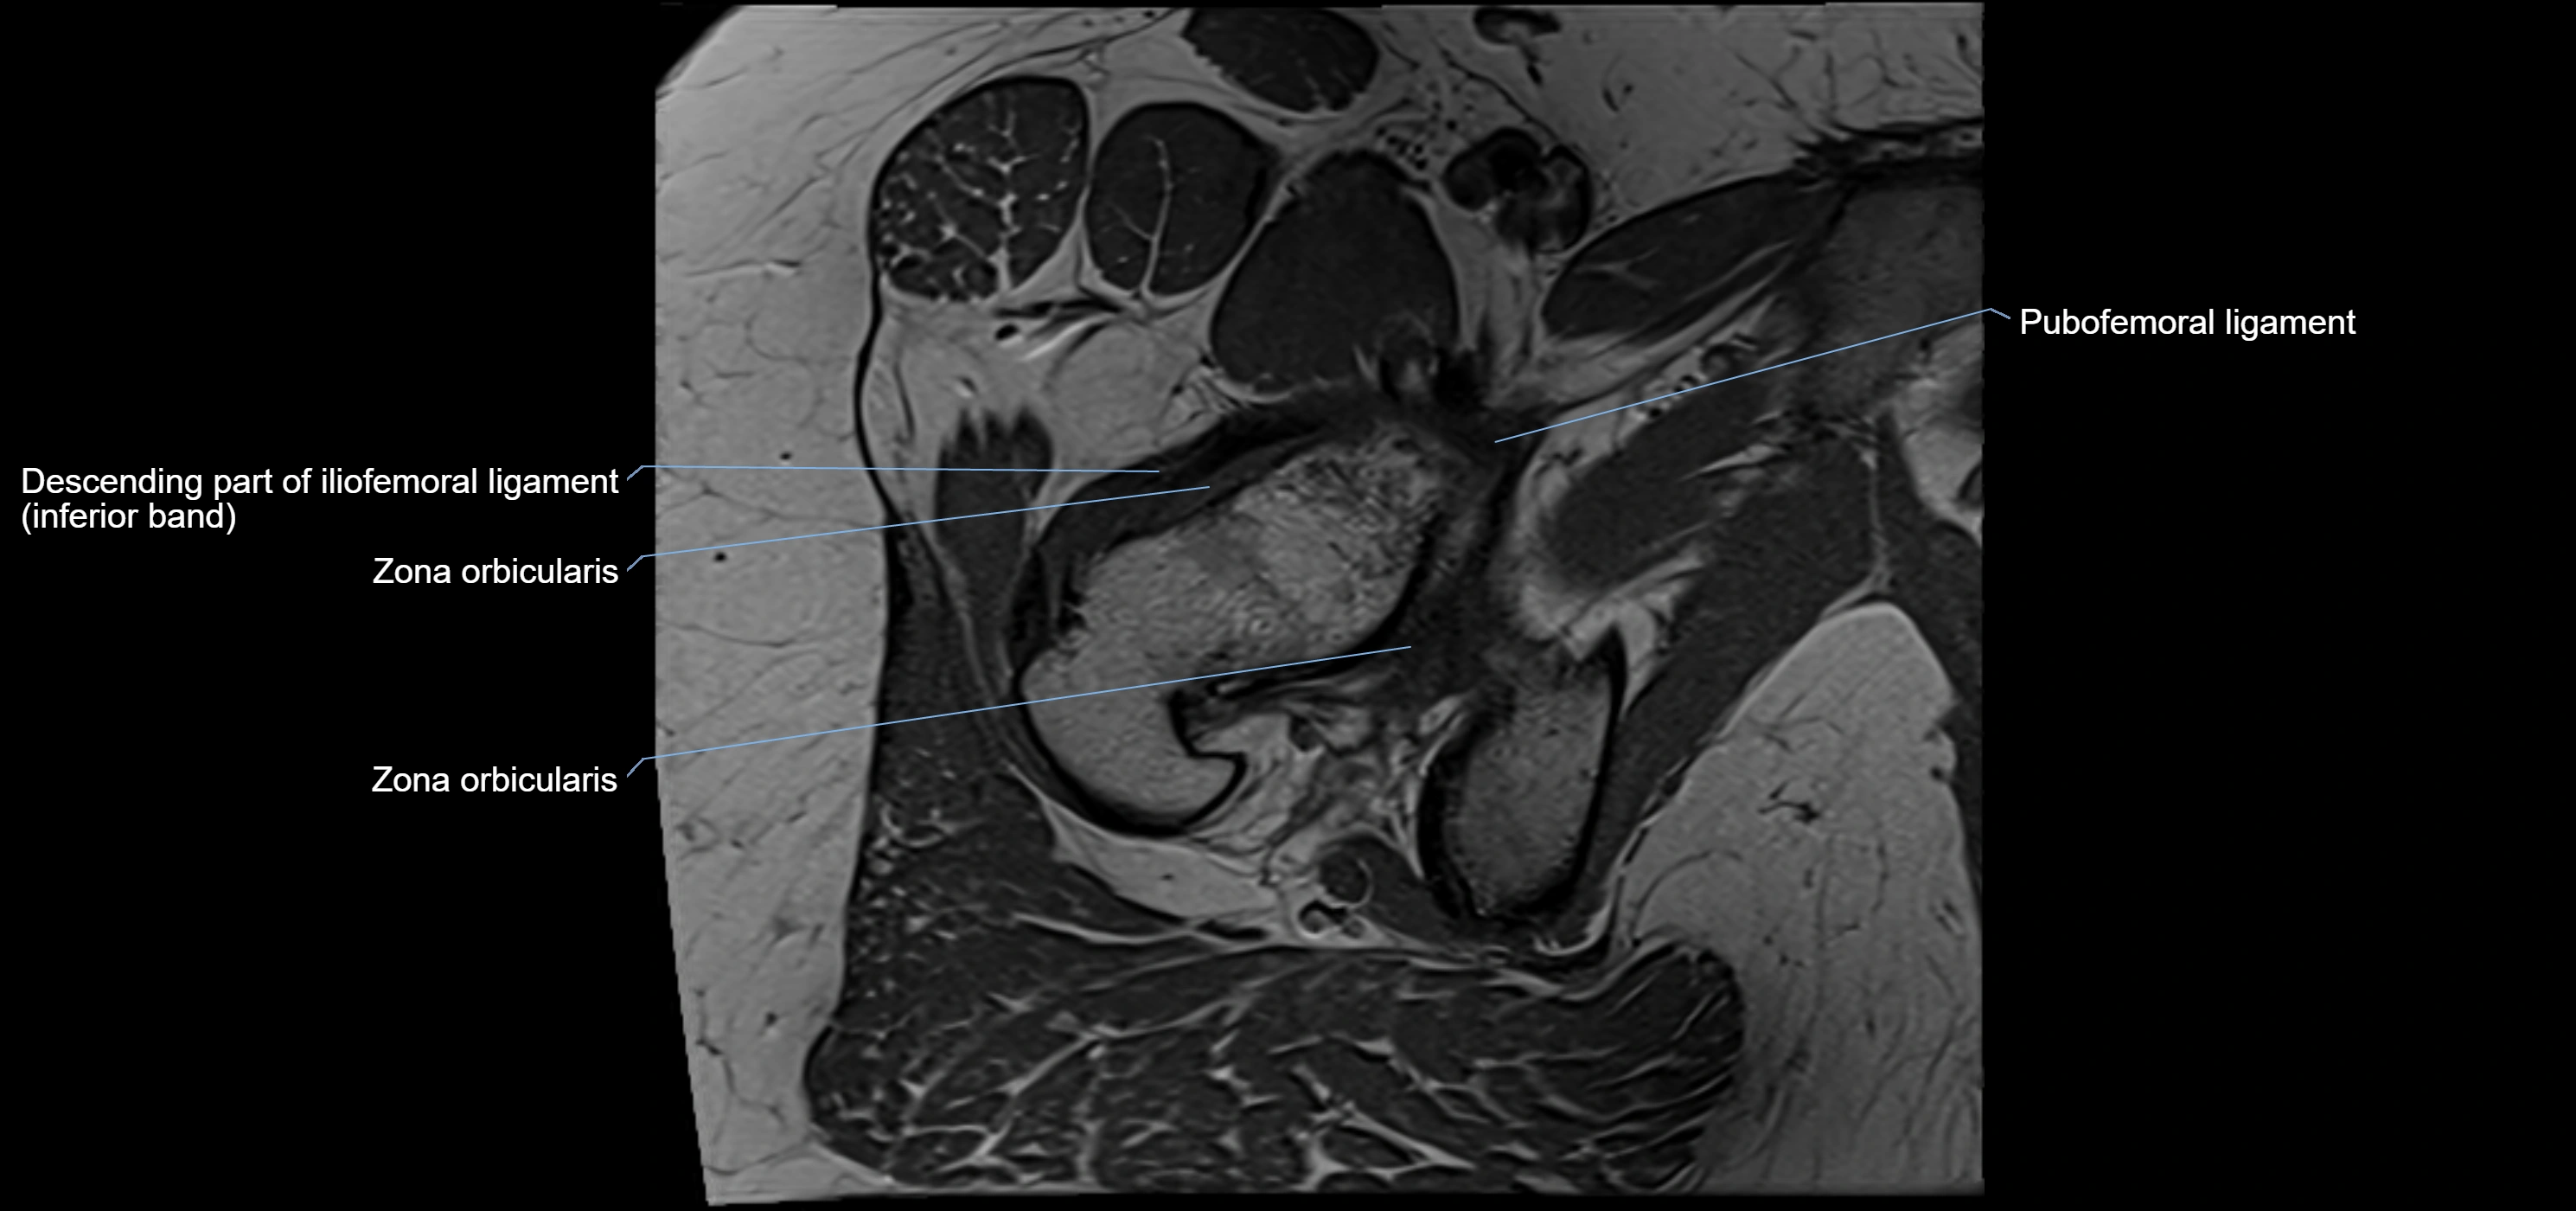

MRI image

image